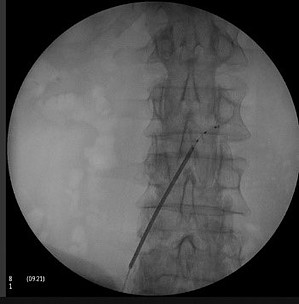

Vor allem bei bestimmten Schmerzsyndromen, die nicht oder nicht mehr ausreichend auf eine medikamentöse Therapie ansprechen, ist es möglich, durch die Rückenmarksstimulation eine Schmerzlinderung zu erzielen. Hierbei werden feine Elektroden in den Rückenmarkskanal eingesetzt, die elektrische Impulse abgeben. Das Einbringen der Elektroden kann in örtlicher Betäubung erfolgen. Die Elektroden werden durch einen Impulsgeber angesteuert, der unter die Haut am Gesäß oder an der Bauchwand der Patient:innen implantiert wird. Die abgegebenen elektrischen Impulse hemmen die Schmerzweiterleitung. Die Schmerztherapie durch Rückenmarksstimulation findet Anwendung nach Verletzung von Nerven oder des Rückenmarkes, aber auch bei Phantomschmerzen und bei behandlungsresistenten Schmerzen durch Durchblutungsstörungen bei Herzkrankheit (Angina Pectoris) und Gefäßkrankheit der Beine (pAVK). Bei der Gefäßkrankheit der Beine (pAVK) kann die Stimulation zudem dazu beitragen, die Durchblutung wieder zu verbessern und die Gliedmaßen zu erhalten. Die Nervenstrukturen bleiben bei der Rückenmarksstimulation erhalten, sodass die Stimulation jederzeit rückgängig gemacht werden kann. Die Einstellungen des Impulsgebers lassen sich von außen – auch durch die Patient:innen – verändern, sodass die Stimulation jederzeit an die Bedürfnisse der Patient:innen angepasst werden kann.